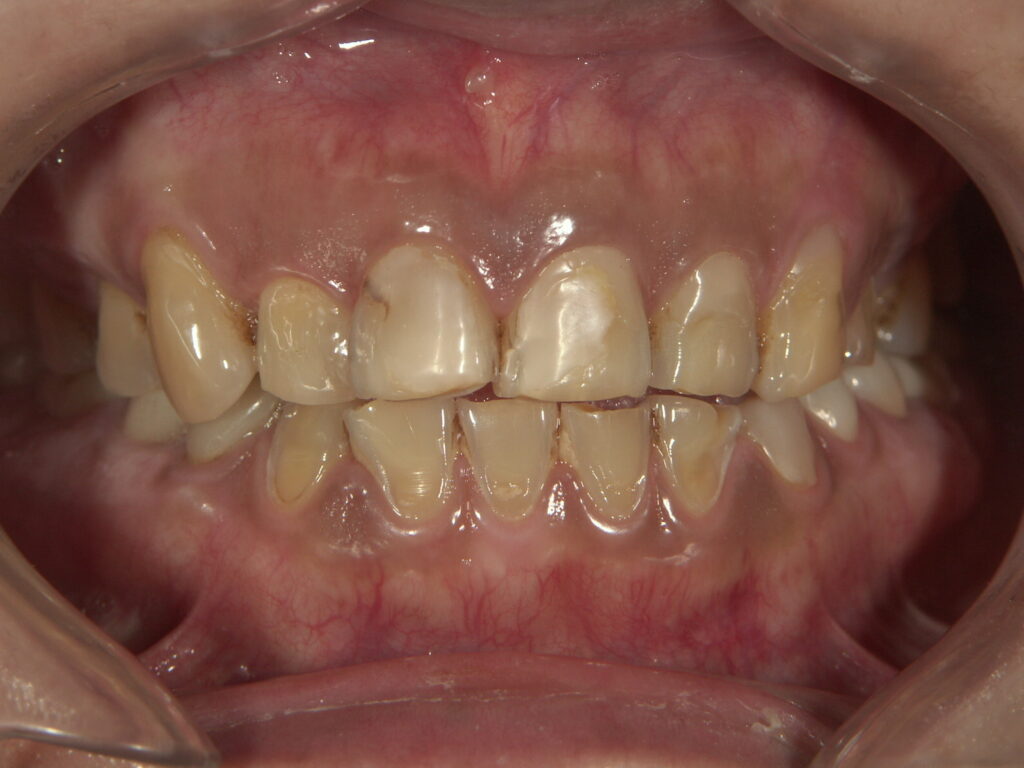

年齢:50代女性